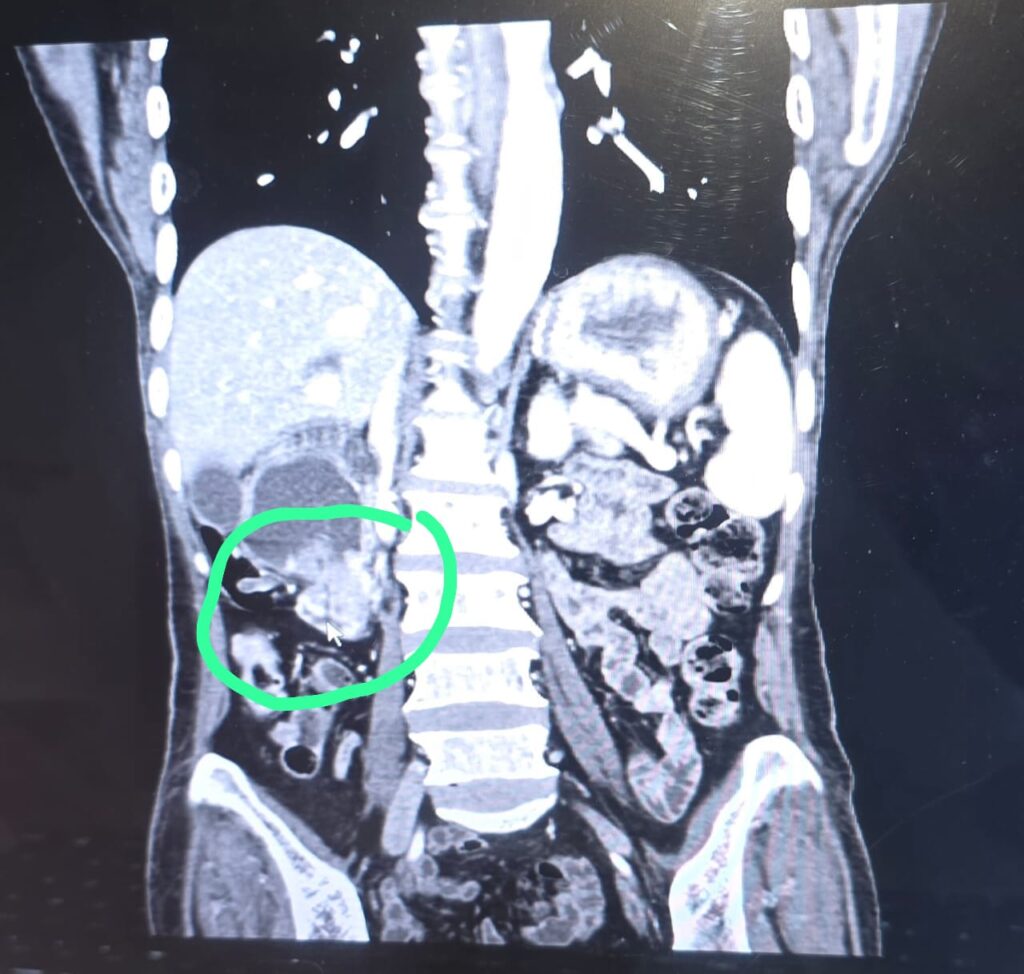

The surgery was particularly challenging due to low blood levels, poor nutrition, a large tumour blocking food passage, a soft pancreas, and disease involvement near the intestine. However, with meticulous planning and teamwork, the surgery was completed successfully.